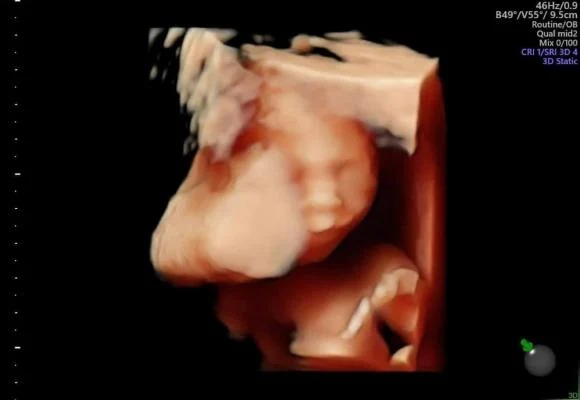

Minh Nguyệt - vợ của nghệ sĩ Tự Long hạnh phúc khoe ảnh siêu âm của con thứ ba.

Mới đây, vợ nghệ sĩ Tự Long bất ngờ công khai hình ảnh siêu âm, tiết lộ đang mang bầu lần 3. Được biết, giới tính của bé thứ ba nhà Tự Long là con trai.

"Ngày đẹp trời đi gặp em trai 1 tí. Có mẹ là có tất cả không có mẹ bên cạnh thiệt thòi đủ thứ thương các chị.... đợi mẹ về nhé!", Minh Nguyệt viết. Trước đó, Tự Long tiết lộ việc vợ bị F0 nên nam nghệ sĩ đã một mình chăm sóc hai con gái nhỏ.